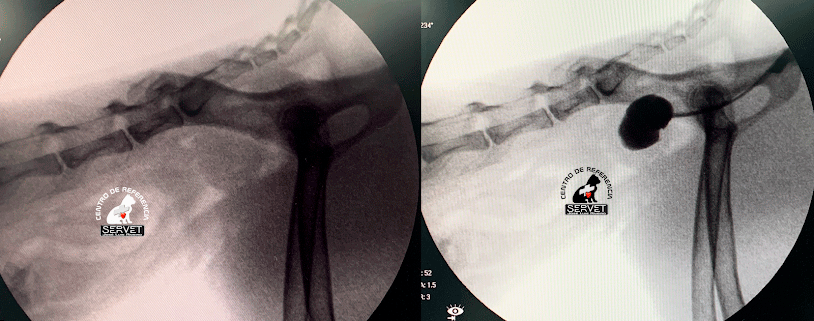

Portografía normal y portografía de shunt portosistémico intrahepático. En el primer video puede verse como el contraste administrado en la vena mesentérica llega al hígado poniendo de manifiesto la ausencia de shunt